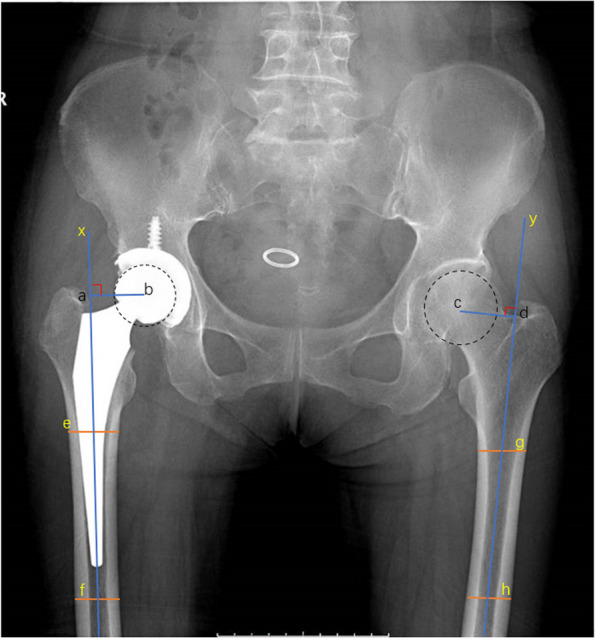

Methods: Collected were data from 350 patients who underwent direct anterior hip arthroplasty between 2008 and 2013, including demographic information, imaging data, Harris hip scores, and surgical complications. Variables, measured radiographically or by CT, included hip offset, leg length discrepancy, component position, and stability within one week after surgery and at the last follow-up. The data were subjected to statistical analysis by using paired t-tests and Pearson chi-square tests.

Results: Data were harvested by follow-up and self-reported questionnaires. The postoperative follow-up lasted for 13.1 years on average (minimum, 10 years; maximum, 15 years), and the overall survival rate of hip prostheses was 96.3%. The mean Harris score at the final follow-up was 91.8 points. After excluding patients with significant preoperative hip deformities, the incidence of postoperative limb inequality (> 5 mm) was 4.9% at the last follow-up, and the incidence of hip offset discrepancy (> 5 mm) was 14.6%. The overall proportion of the acetabular components located in the Lewinnek safe zone was 77.7%, whereas the proportion of femoral prostheses in the safe zone (< 3° inclination) was 94.0%. Based on the revised data and the last follow-up imaging, the total proportion of acetabular and femoral prostheses with a radiolucence of > 2 mm was 5.1%.